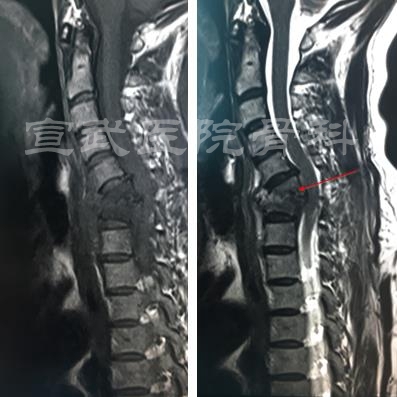

2016年12月26日(左)VS2017年1月13日(右)

C5-6

MRI

C6-7

与会专家就病例相关诊断及治疗方案就行讨论。患者颈部疼痛伴有右上肢神经功能损害,伴有发热,最高温度40°,经抗生素治疗体温控制良好,一月前后两次核磁显示椎间盘及椎体骨质破坏进展迅速,结核及布鲁氏菌相关诊断阴性感染,术前诊断非特异性感染可能性大。

有专家表示,患者颈椎病灶破坏明显,呈局部后凸,稳定性极差,影像可见椎管内占位信号及脊髓受压,保守治疗风险较大,在场专家均建议手术治疗。